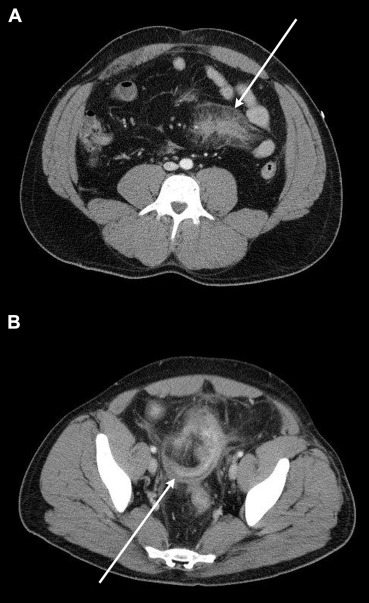

A 32-year-old male presented to our trauma center following a motorcycle accident. He was found to have a closed head injury, rib fractures, left shoulder dislocation, humerus fracture, and open fracture of the left tibia and fibula. A computed tomography (CT) scan of the abdomen with contrast showed a 7 × 4 cm2 mesenteric hematoma (Fig. 1A). A closed reduction of the shoulder dislocation, and an open reduction and internal fixation of his tibia and fibula fractures were performed. He was discharged from the hospital after 1 week of observation. As the patient had open fractures on admission, he received a 10-day course of antibiotics (7 days during the hospital stay and 3 days after his discharge). At the time of discharge, the patient had no fever and was tolerating a regular diet. His abdomen was soft and nontender on examination. His complete blood count showed a normal white blood cell count of 9.03 k/μL (k/μL = thousands per cubic milliliter) (normal range = 4.0–11.0 k/μL). The patient returned to the hospital 4 weeks after discharge (5 weeks post-trauma), complaining of abdominal pain on sitting up and in a standing position. He did not have a fever, was tolerating regular food, and had normal bowel movements. There was no evidence of peritoneal signs on abdominal physical examination. A repeat CT scan of the abdomen with contrast was performed, which showed a thickened narrowed loop of the small bowel adjacent to a mesenteric hematoma at the level of the distal ileum (Fig. 1B). His white blood cell count was 7.59 k/μL (normal range = 4.0–11.0 k/μL). He was discharged home but re-presented 1 week later (6 weeks post-trauma) with signs of acute abdomen. His white blood cell count was measured at 18.94 k/μL (normal range 4.0–11.0 k/μL). An exploratory laparotomy was performed. Intraoperative findings included a phlegmon in the mid lower abdomen with a perforated thickened loop of the small bowel and about 300 mL of purulent material in the abdomen (Fig. 2). He underwent resection and anastomosis of the small bowel.

(A) Abdominal computed tomography immediately after trauma and (B) 5 weeks ...

Figure 1.

(A) Abdominal computed tomography immediately after trauma and (B) 5 weeks post-trauma, showing the mesenteric hematoma (white arrow in Fig. 1A) and the stenotic loop of the small bowel adjacent to the hematoma (white arrow in Fig. 1B).